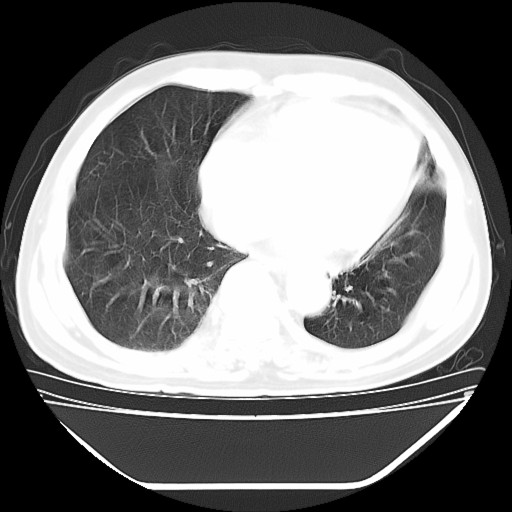

以下是引用hhcckk在2009-5-29 10:34:00的发言:[br]左下肺片絮状边缘模糊影,考虑感染,建议治疗后复查[br]